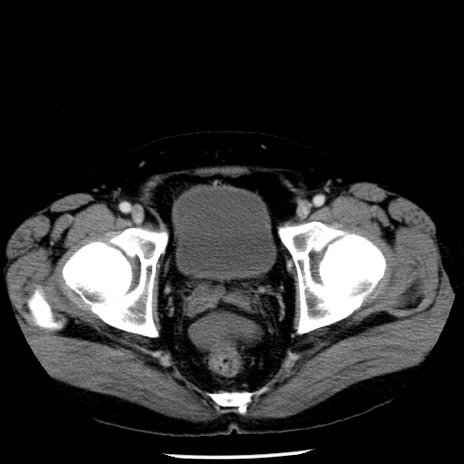

症例29(横断像)

【症例】40歳代男性

【現病歴】2日前から胃痛あり。徐々に周期的な激痛に変化した。本日になっても激痛があるため受診。

【身体所見】意識清明、BT 38-39℃台あり、腹部:膨満、やや硬、右下腹部に圧痛あり。

【データ】WBC 8500、CRP 23.26